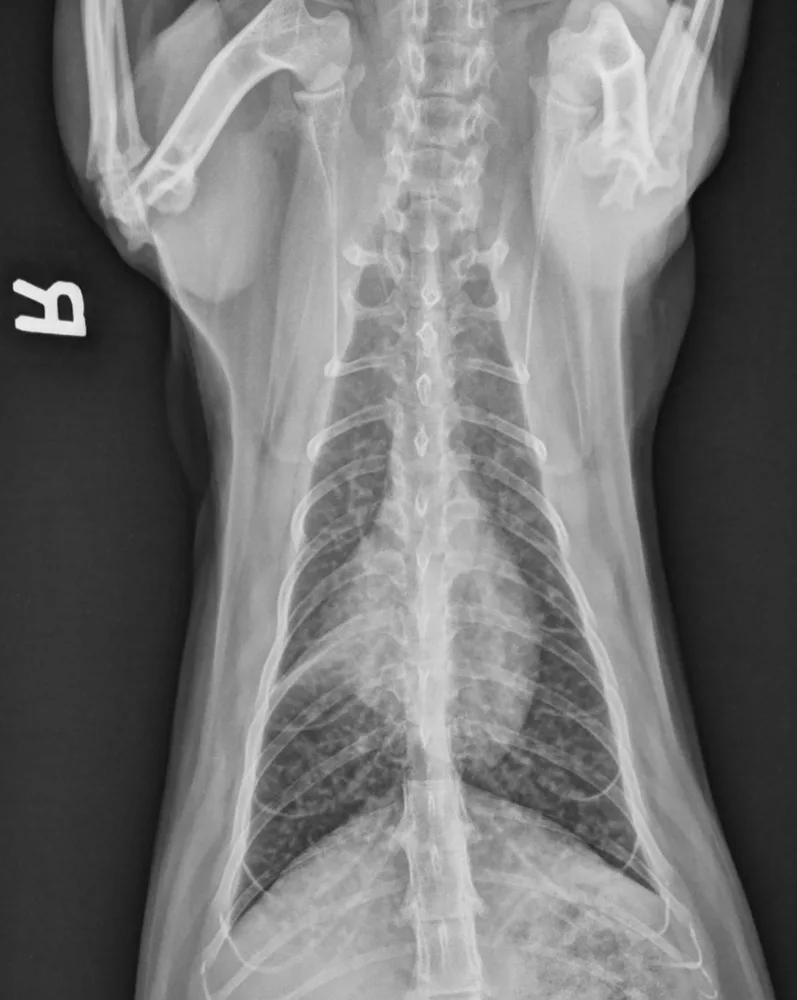

Ventrodorsal thoracic radiograph of an asthmatic cat

Physical examination may be normal or may reveal tachypnea, inducible cough on tracheal palpation, and/or abnormalities on thoracic auscultation (eg, increased bronchovesicular sounds, expiratory wheezes). Classic radiographic findings include a diffuse bronchial or bronchointerstitial pattern, hyperinflation due to air trapping, and/or collapse of the right middle lung lobe due to mucus plug obstruction (Figure 1).3,4 Because ≈20% of asthmatic cats have normal thoracic radiographs, asthma should remain on the differential list for any cat with respiratory distress and normal thoracic radiographs.5 In addition, a bronchial or bronchointerstitial pattern is also the predominant pulmonary pattern seen in cats with chronic bronchitis and/or heartworm-associated respiratory disease, making it challenging to differentiate these conditions from asthma via only physical examination and radiography.

FIGURE 1

Ventrodorsal thoracic radiograph of an asthmatic cat demonstrating a diffuse bronchial pattern and collapse of the right middle lung lobe, which developed secondary to mucus accumulation and resulted in atelectasis